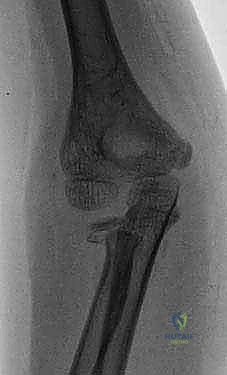

- الكسر المنزاح (Displaced Fracture): تنفصل نهايتا العظم المكسور عن بعضهما وتفقدان المحاذاة الصحيحة، مما يتطلب إرجاع العظم إلى مكانه (الرد) سواء يدوياً أو جراحياً.

يعتمد التشخيص الأساسي على التصوير بالأشعة السينية (X-rays) من زوايا متعددة (أمامية وجانبية) لتشمل مفصلي الركبة والكاحل. في بعض الحالات المعقدة، خاصة تلك التي تمتد إلى المفاصل أو صفائح النمو، قد يطلب الدكتور هطيف إجراء تصوير مقطعي محوسب (CT Scan) أو رنين مغناطيسي (MRI) للحصول على صورة ثلاثية الأبعاد ووضع خطة جراحية فائقة الدقة.

عندما يكون الكسر غير مستقر، أو مضاعفاً، أو يهدد صفائح النمو، يصبح التدخل الجراحي ضرورة حتمية. يستخدم الدكتور هطيف أحدث التقنيات العالمية في تثبيت عظام الأطفال:

- المسامير النخاعية المرنة (Flexible Intramedullary Nails - TENs): وهي تقنية حديثة ومثالية للأطفال. يتم إدخال مسامير مرنة من التيتانيوم داخل تجويف العظم عبر شقوق صغيرة جداً (Minimally Invasive). تعمل هذه المسامير كدعامة داخلية تسمح للعظم بالالتئام بسرعة دون فتح جراحي كبير، وتوفر ثباتاً ممتازاً.

- الشرائح والمسامير (Plates and Screws): تستخدم في الكسور القريبة من المفاصل أو التي تتطلب تثبيتاً صلباً ومحاذاة دقيقة جداً.